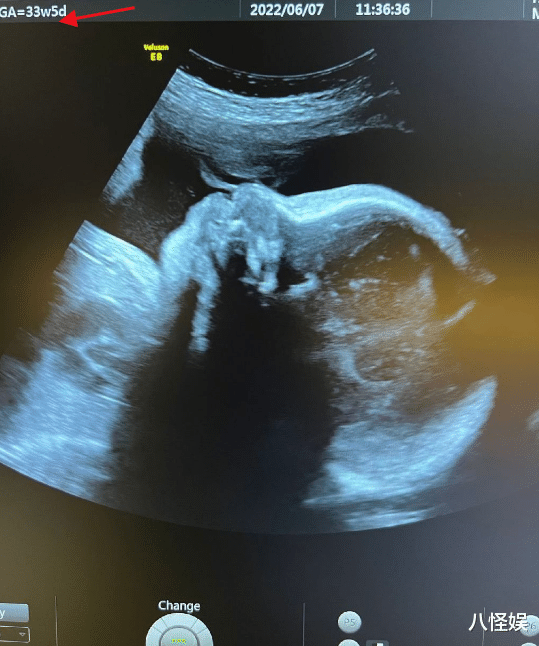

陈燃还分享出最新孕检B超照 , 从B超照来看 , 6月7日进行产检的陈燃 , 当时已经怀孕33周+5 , 进入孕晚期的她肚中宝宝基本已经成型 , 不过 , 如果不是专业人员 , 并不能通过这样一张B超照判定出宝宝性别 ,那么问题来了 , 陈燃是通过何种手段知道肚中二胎宝宝性别的呢?